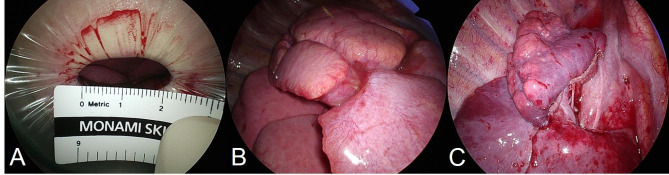

A decision was made to conduct the surgery jointly, having both specialties participate. Under general anesthesia, lung-sparing resection was performed through uniportal VATS, hoping to to reduce surgical stress and preserve normal parenchyma. The patient’s height was 152 cm and weight was 40 kg, so thoracoscopic access was considered possible. This was followed by resection of the ranula. The patient was placed in left lateral decubitus position, using a double-lumen endotracheal tube for single-lung ventilation. A small surgical incision (2.3 cm) was made in anterior axillary line at fourth intercostal space (Fig. 2A). The working port was covered by a small wound protector (W-Shield Retractor X-S; SNT Medical, Seoul, Korea), and a 5-mm, 30° scope was stationed at its upper rim by the surgical assistant. Various instruments (i.e., curved suction tip, grasping tools, and articulating endostaplers) were inserted through the single incision.

Fig. 2.

(A) Small working incision (2.3 cm) covered by wound protector. (B, C) Surgical view before and after uniportal VATS RUL anterior segmentectomy

The anterior segment of RUL was generally consolidated, with focal abscess formation (Fig. 2B). Close inspection was done to ensure there were no cystic areas in adjacent apical and posterior segments. The first step was to open the minor fissure via tunnel technique. Initially, we dissected the major fissure to locate interlobar arteries (as a later exit point for stapling). Mediastinal pleura was subsequently opened to dissect between upper and middle lobar veins. Once the central vein was identified, a clamp was placed lateral to middle lobar artery to include central vein. The minor fissure was finally transected, using a 45-mm stapler with a purple load. Mediastinal pleura abutting upper lobar artery was quite dense, requiring careful dissection to expose the anterior segmental pulmonary artery. Both artery and vein were isolated and divided using silk ligatures. Next, thorough lymphadenectomy (levels 11–13) was undertaken, exposing the anterior segmental bronchus. Before proceeding, two-lung ventilation was initiated, checking for inflation of RUL apical and posterior segments. Thereafter, we divided anterior segmental bronchus (45-mm stapler with purple load) and injected indocyanine green (ICG) to mark the intersegmental plane. RUL anterior segmentectomy was thus completed by dividing along this plane, using three purple-loaded 45-mm staplers.

The resected specimen was placed in an endocatch bag to retrieve it through the working port. No diseased areas (consolidated and cystic lesions) were found in the remaining apical and posterior segments of RUL, right middle lobe and right lower lobe of the thoracoscopic field of view (Fig. 2C). A water sealing method was performed to check for air leaks, and no air leaks were identified. Following irrigation, intercostal nerve blockade (bupivacaine, 1 mL) was performed at lower margins of third through seventh ribs. A 16-French chest tube was then inserted at the lower incisional edge, and the working incision was closed in layers. For skin closure, unidirectional absorbable barbed suture (V-Loc 180; Medtronic, Minneapolis, MN, USA) was used, leaving a thread attached. We connected the chest tube to a digital drainage system (DDS, Thopaz; Medela AG, Baar, Switzerland) with a suction pressure of -15 cm H20, and the patient was moved from lateral decubitus to supine position for resecting the ranula.